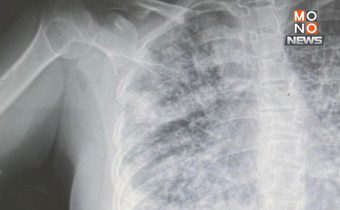

EVALI หรือ E-cigarette or Vaping product use Associated Lung Injury เป็นภาวะปอดอักเสบรุนแรงจากการใช้บุหรี่ไฟฟ้า โดยผู้ป่วยส่วนใหญ่จะมีอาการคล้ายติดเชื้อ ได้แก่ ไข้ ไอ เหนื่อยหนาวสั่น ปวดเมื่อย และมากกว่าร้อยละ 70 มีอาการคลื่นไส้ อาเจียนร่วมด้วย ภาพเอกซเรย์และ CT Scan พบปอดผิดปกติ มีลักษณะเป็นฝ้าขาว ส่งผลให้การหายใจลำบากอย่างรุนแรง